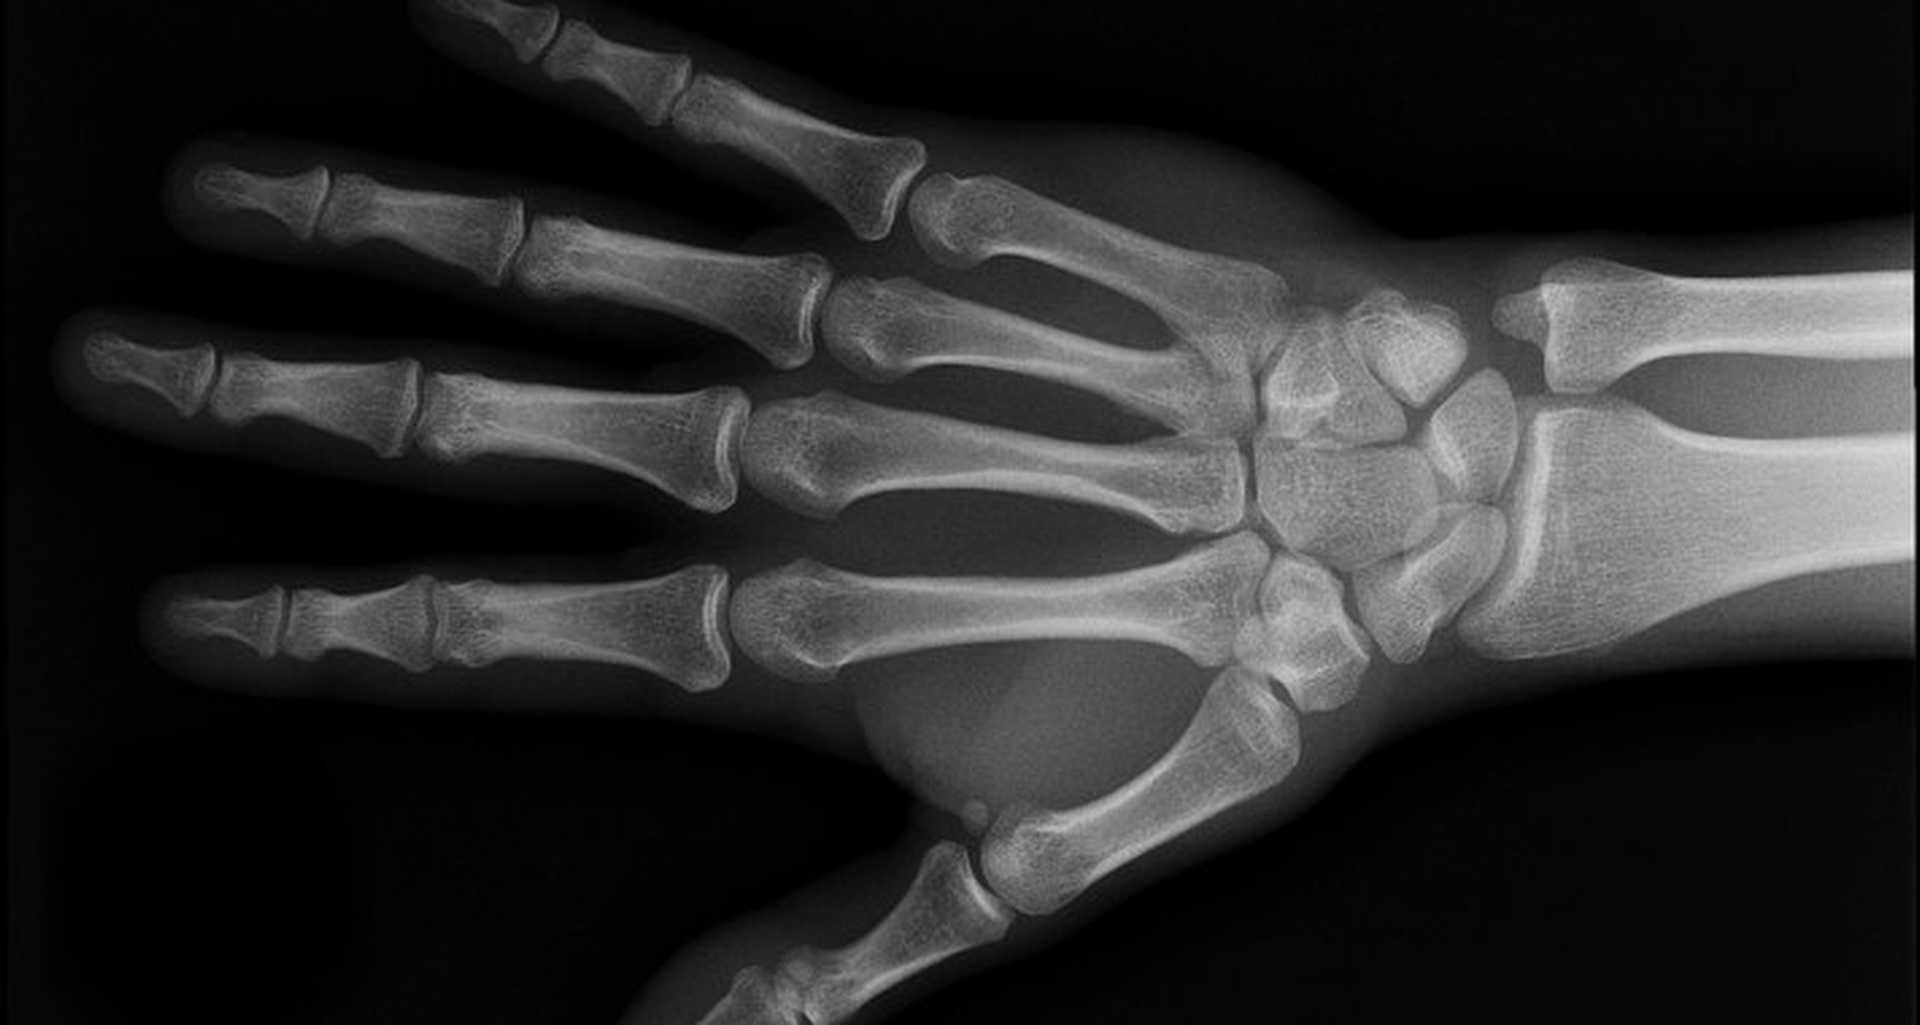

8 Kasım 1895 akşamı Röntgen laboratuvarında, katot-ışını tüplerinin ışığı nasıl yaydığını inceliyordu. Katot ışınlarının etkisinden çok uzakta bulunan parlayan bir flüoresan ekran birden dikkatini dağıttı. Parlaklığın kaynağını araştırmaya çalıştığı için laboratuvarını haftalarca terk etmedi. Işınları takip etmek amacıyla kart parçalarını onların önüne koydu fakat ışınlar, kartların olup olmadığına bakmaksızın onların içinden rahatça geçerek ekranın parıldamasını devam ettirdi. Daha sonra ışınları metalle engellemeye çalıştı. Ancak ince bakır ve alüminyum parçaları da kart gibi şeffaftı. Ekranın önüne bir parça kurşun taşıdı ve gölgesini dikkatle izledi. Ardından onu şaşkınlıkla düşürdü çünkü ekranın karşısında el kemiklerinin karanlık iskelet şeklini görmüştü. Ne gördüğünden hala kuşkuluyken, kalıcı bir kayıt için bazı fotoğraf filmleri çıkardı.

Birkaç hafta sonra eşi Bertha’yı laboratuvara davet etti ve el kemiklerinin evlilik yüzüğü ile beraber gölge grafiğini çok net olarak çıkardı. Bu, fotoğraf tarihindeki en ünlü görüntülerden biridir ve iki hafta içinde uluslararası bir ün kazanmıştır.

- Hand with Rings: https://www.nobelprize.org/nobel_prizes/physics/laureates/1901/rontgen-photo.html